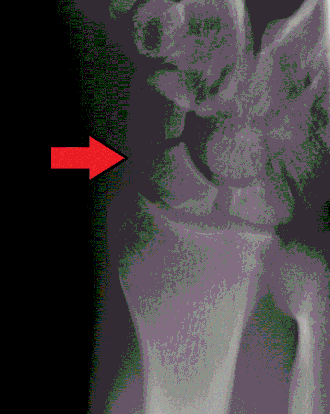

Fratura do escafoide

| Raio-X de uma fratura do escafoide | |